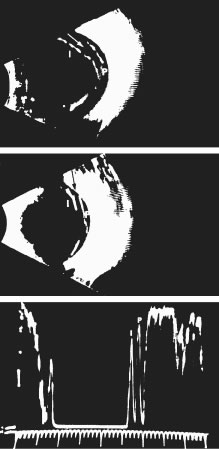

The posterior vitreous cortex is 100 to 110 μm thick117 and consists of densely packed collagen fibrils (Fig. 6). There is no vitreous cortex over the optic disc (Figs. 3A and 7), and the cortex is thin over the macula because of rarefaction of the collagen fibrils.117 The prepapillary hole in the vitreous cortex can sometimes be visualized clinically when the posterior vitreous is detached from the retina. If peripapillary glial tissue is torn away during posterior vitreous detachment (PVD) and remains attached to the vitreous cortex around the prepapillary hole, it is referred to as Vogt's or Weiss's ring. Vitreous can extrude through the prepapillary hole in the vitreous cortex (see Fig. 3A) but does so to a much lesser extent than through the premacular vitreous cortex (see Figs. 2B and D and 6). Jaffe118 has described how vitreous can extrude into the retrocortical space created following PVD and has proposed that persistent attachment to the macula can produce traction and certain forms of maculopathy.119,120 Although there are no direct connections between the posterior vitreous and the retina, the posterior vitreous cortex is adherent to the ILL of the retina, which is actually the basal lamina of retinal Müller's cells. The exact nature of this adhesion between the posterior vitreous cortex and the ILL is not known but probably results from extracellular matrix molecules.121–123

Fig. 6. Ultrastructure of human vitreous cortex. Scanning electron microscopy demonstrates the dense packing of collagen fibrils in the vitreous cortex. To some extent this arrangement is exaggerated by the dehydration that occurs during specimen preparation for scanning electron microscopy.